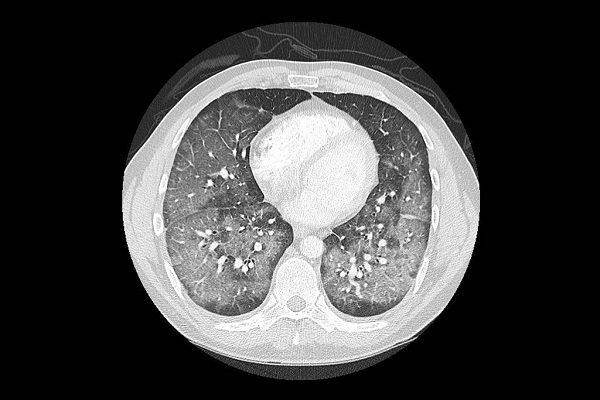

En las tomografías pulmonares, las enfermedades al principio lucen como una neumonía viral o bacteriana grave, pero los análisis no dan señales de infección. “Hemos llevado a cabo muchas pruebas buscando bacterias y virus, pero dan negativo”, dijo Dixie Harris, neumóloga de cuidados intensivos en Salt Lake City, que ha examinado a cuatro pacientes que sufren ese padecimiento y revisó los archivos de nueve más en el estado.

Algunos pacientes sufren otro padecimiento conocido como neumonía lipoidea, dijeron los médicos. Cuando los aceites vapeados llegan a los pulmones, estos los tratan como un objeto extraño y detonan una respuesta inmune, que provoca inflamación y la acumulación de líquidos, lo cual puede resultar en una neumonía lipoidea.